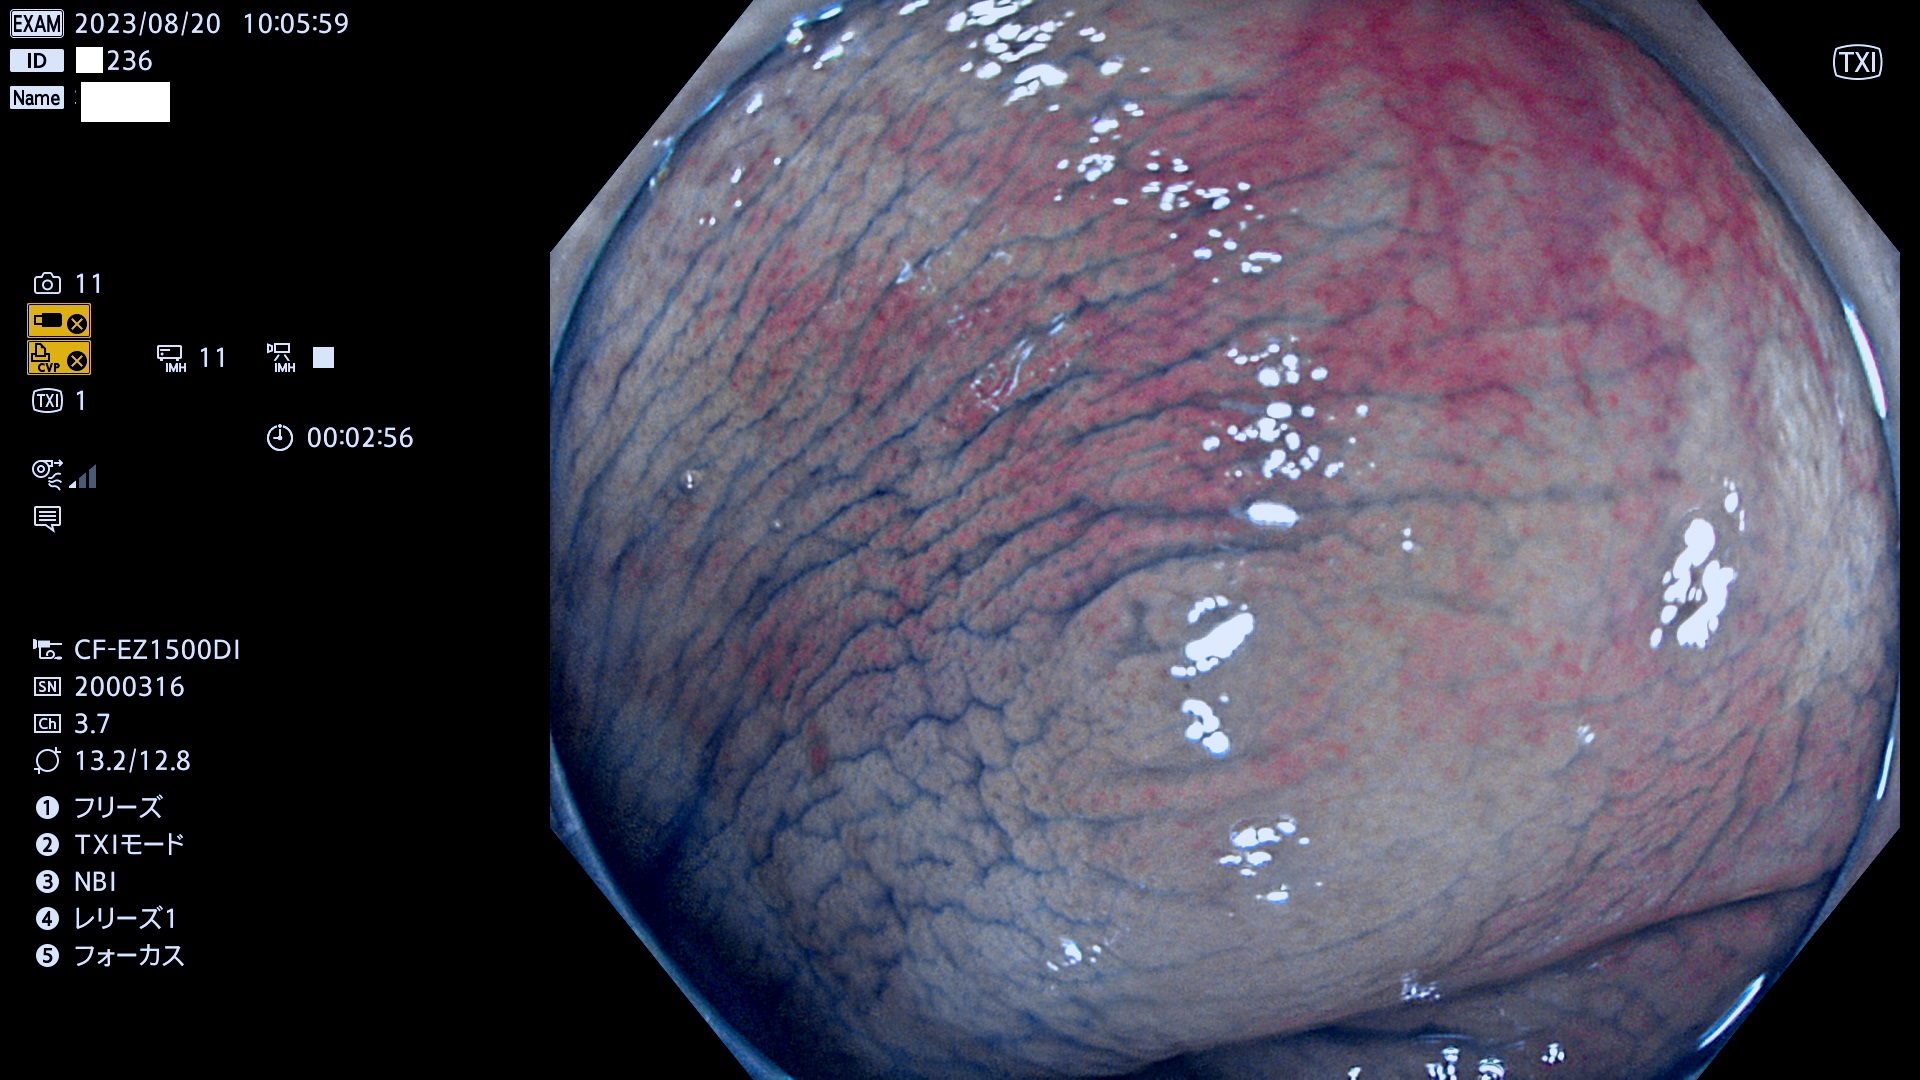

表面型腺腫(Flat Adenoma)の中で、完全に平坦な物をUb、陥凹している物をUcと呼びます。平坦隆起型(Ua)よりも、発見が難しく危険な病変です。このタイプは「内視鏡後・大腸癌の重要犯人」であり、この発見率は「腺腫発見率」よりも、重要な意味があります。

毎週の検査(木・金・土・日)に発見されたUb、Uc型・腺腫を、その週の日曜の夜にUPし1週間、提示します。

抽出の対象期間 2023年8月17日(木)〜8月20(日)の4日間(48件の検査)11件